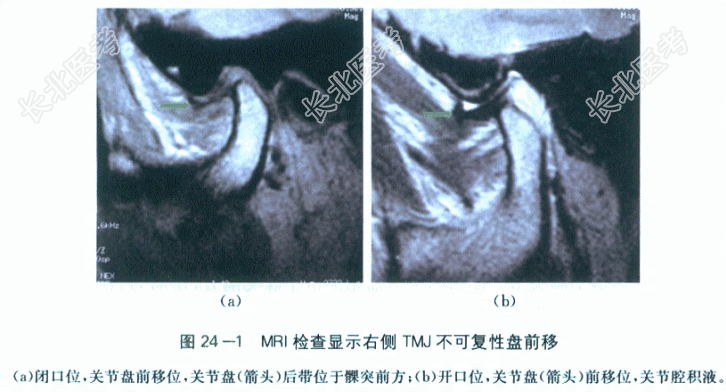

面部无红肿。张口度2.5cm,张口型右偏。双侧颞下颌关节区张闭口未及弹响,右侧髁突动度较左侧小。右侧耳屏前压痛(+),左耳屏前、双侧乙状切迹及双侧咬肌区均未及压痛。口内牙列完整,咬合关系正常,牙齿无松动、无叩痛。口腔卫生良好,口内牙龈及其他黏膜色泽正常,无破溃、肿胀及压痛。5.影像学检查MRI:张闭口过程中关节盘均位于髁突前上方,右侧颞下颌关节关节盘不可复性前移位(见图24-1)。患者口腔卫生良好,咬合关系正常,牙列完整,牙齿无松动及叩痛。口内牙龈及黏膜无红肿及压痛。(3)张口度及张口型的检查:张口度是指受检者大开口时,上、下颌中切牙近中切角之间的垂直距离。正常开口度平均为3.7cm,小于3.7cm为张口受限。开口型是指下颌自闭口到张大的整个过程中下颌运动的轨迹。正常成人开口型不偏斜,呈垂直向下,而颞下颌关节紊乱患者常出现开口型异常(偏斜或扭曲)。患者张口度2.5cm,属于张口中度受限,张口型右偏。(4)颞下颌关节的检查,通过患者的开闭口运动、前伸运动和侧方运动,检查关节功能是否正常,有无疼痛、弹响和杂音;两侧关节动度是否一致,有无偏斜;开口度和开口型是否正常,以及在开闭口运动时是否出现关节绞锁等异常现象。患者张口度变小,张口型右偏,双颞下颌关节未及弹响,右侧耳屏前有压痛。(5)咀嚼肌检查,检查颞肌、咬肌等咀嚼肌群的收缩力,触压其是否有疼痛,观察两侧是否对称、协调。在口内可按咀嚼肌的解剖部位进行左右对比,检查有无压痛等异常。患者各咀嚼肌区无压痛。